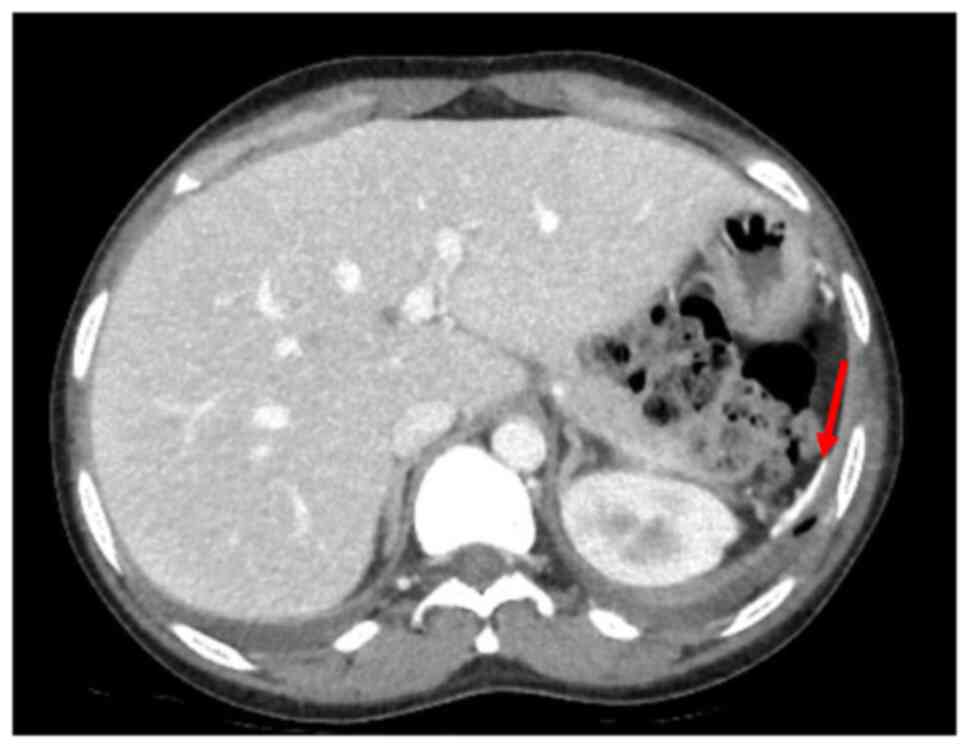

Blood tests revealed mild anaemia with a reduced red blood cell (RBC) count [haemoglobin (Hb), 9.8 g/dl; RBC, 3.34x106/mm3, normal white blood cell count (WBC), increased C-reactive protein (CRP) levels (2.38 mg/dl) along with high erythrocyte sedimentation rate levels (104 mm/h), increased total bilirubin levels (2.85 mg/dl), aspartate aminotransferase at 83 U/l and alanine aminotransferase at 56 U/l. Creatinine levels and liver function marker (coagulation and albumin) levels were normal (creatinine level, 0.56 mg/dl; international normalized ratio, 0.98; and albumin, 3.8 g/dl). Hepatitis B virus (HBV) and hepatitis C virus (HBC) along with human immunodeficiency virus (HIV) tests were negative. A chest X-ray revealed right medio-basal lung consolidation with a perivascular interstitial thickening (Fig. 1). Thorax computed tomography (CT) scan images (acquired before and after contrast administration, using a SOMATOM® Definition Flash scanner; Xenetix, 350 mg/ml; Siemens AG) revealed bilateral ground glass opacities with interlobular septal thickening, lower lobes consolidations and bilateral pleural effusion (Fig. 2), whereas an abdomen CT scan revealed homogeneous hepatomegaly, and a 3 cm densely calcified spleen (Fig. 3).

Figure 3

Abdomen computed tomography scan demonstrating hepatomegaly, and a miniscule densely calcified spleen (red arrow).